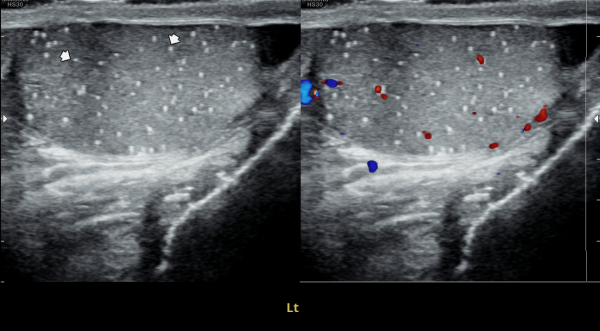

좌측고환의 초음파 검사상 또한 고환의 미석증이 관찰되는 사진입니다.(NIH:24)

On the ultrasound examination of the left testis, multiple tiny echogenic foci without acoustic shadowing are again observed, consistent with testicular microlithiasis.(NIH:24)

주 2회 14주 동안 정관과 사정관, 정낭 그리고 전립선의 표적 치료후 치료되고 있는 좌측 고환 미석증들의 초음파사진입니다.(NIH:13)

This ultrasound image shows improvement of left testicular microlithiasis after targeted treatment of the vas deferens, ejaculatory ducts, seminal vesicles, and prostate.

The treatment was performed twice a week over a period of 14 weeks, and the previously observed tiny calcifications in the testis are gradually improving, suggesting better circulation and recovery of the reproductive tract.(NIH:13)

These images demonstrate that microlithiasis is present bilaterally, not only on the right side but also within the left testis.

Such findings are characterized by the deposition of microscopic calcifications within the seminiferous tubules.

Clinically, testicular microlithiasis is often asymptomatic but may be associated with chronic testicular pain, infertility, or underlying urogenital conditions, and therefore follow-up and further evaluation may be warranted.